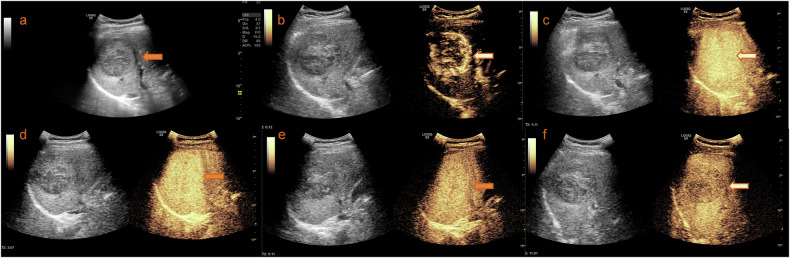

Fig. 3.

Imaging and diagnosis of HCC. a Identification of a liver mass located in the right lobe, discovered during a routine physical examination. b Enhancement of the mass following the injection of contrast agent in the arterial phase and portal venous or late phase. c–f Kupffer phase imaging shows early washout of the contrast agent from the mass. Therefore, this lesion could be accurately diagnosed as HCC under the KLCA-NCC and APASL guidelines